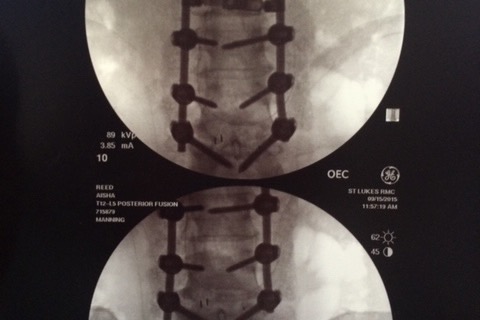

Aisha was diagnosed with degenerative disc disease and scoliosis. Her first surgery in 2015 was a spinal fusion of six vertebrae. Rods and screws were implanted to stabilize and straighten her back.

(Screws and rods that came loose after the first surgery.)

(Screws and rods that came loose after the first surgery.)

When this did not resolve her pain, the second surgery in 2018 removed the rods, one of which was broken in two. Five of the 12 screws from the previous surgery were loose because they were not long enough. This second surgery did not offer the hoped-for resolution of pain issues. In fact, the surgery and her bone spurs, herniated discs and bulging discs increased the nerve pain in her legs.

Aisha was diagnosed with degenerative disc disease and scoliosis. Her first surgery in 2015 was a spinal fusion of six vertebrae. Rods and screws were implanted to stabilize and straighten her back.

(Screws and rods that came loose after the first surgery.)

(Screws and rods that came loose after the first surgery.)When this did not resolve her pain, the second surgery in 2018 removed the rods, one of which was broken in two. Five of the 12 screws from the previous surgery were loose because they were not long enough. This second surgery did not offer the hoped-for resolution of pain issues. In fact, the surgery and her bone spurs, herniated discs and bulging discs increased the nerve pain in her legs.